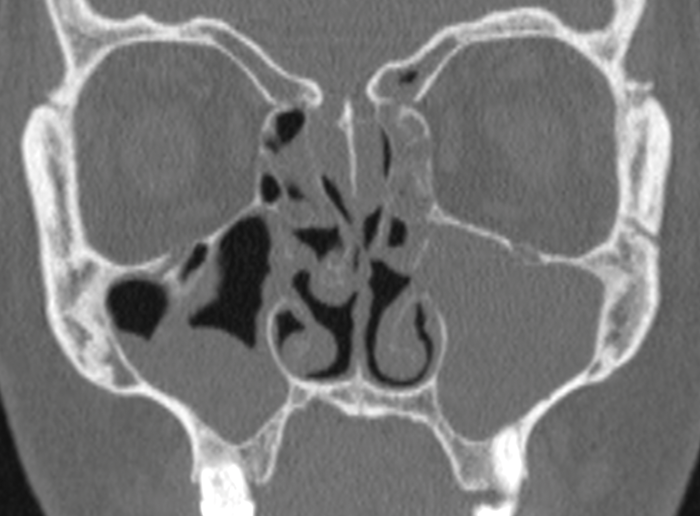

Preoperative sinonasal CT imaging is essential to FESS surgery. Ideally the CT data should be provided in thin-slices (less than 1mm thick) including the full volume of the paranasal sinuses. The images should be available during surgery in a 3 axis viewer, preferably one with the facility for multiplanar reconstruction (MPR).

Before the case, it is helpful to perform an MPR to align the axial slices with the palate and skull-base, while correcting any angulation of the coronal images to obtain symmetric views. Window-levels are optimised for bone definition, rotation corrected for each view, and the views maximised by zoom. We then study the scans from three different perspectives as follows.

Studying and understanding an individual patient’s radiological anatomy will facilitate a safe and effective dissection. It is usually easiest to identify deviations from ‘normal anatomy’, recognising features such as a concha bullosa, Onodi, and Haller cells to allow operative orientation and maintain safety. The complex anatomy of the frontal recess is defined by the relationships of the basal lamellae of the uncinate process and ethmoidal bulla and their insertions into the lamina papyracea and skullbase. Understanding this anatomy, then demonstrating the same during surgery by probing will then facilitate a complete, safe, and mucosa preserving technique.

Cribriform plate - defects, deep (vulnerable) lateral lamellae, or disorientating asymmetry.

Lamina papyracea - defects (from prior surgery or injury) or a low uncinate orbital insertion.

Onodi cells - most easily seen on coronal views, especially after a well performed MPR.